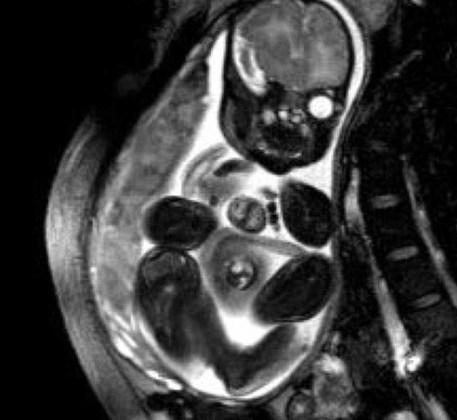

据英国《每日邮报》1月24日报道,美国得克萨斯州一名小女婴患有极为罕见的先天性心脏异位症状,她出生时心脏就长在胸腔外。万幸的是,得州儿童医院的医生妙手回春,将心脏放回了原位。

小女婴名叫奥德利娜・卡德纳斯,她的母亲艾希礼在孕期第16周接受常规检查时发现了她的异状。心脏异位是一种非常罕见的疾病,患者90%会胎死腹中或者在生下来几天内不治身亡。

医生给奥德利娜做了手术,把心脏放回到她体内。